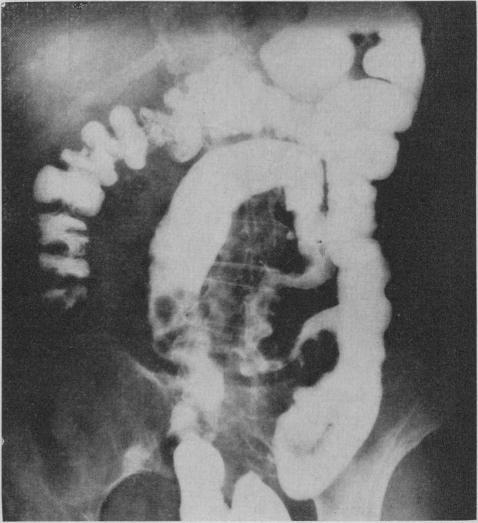

Pneumatosis cystoides intestinalis involving the left side of the colon has been infrequently described. The condition was recognized 234 years ago when it was discovered in a cadaver. It was not until 1946, however, that a description of this lesion appeared in the radiological literature of North America. Pathologically, it is characterized by the presence of subserosal or submucosal cysts, varying from one millimetre to several centimetres in diameter. The complications of this process are pneumoperitoneum and intestinal obstruction. Three patients are described, the first of whom had partial bowel obstruction. Radiolucent gas-filled cysts along the bowel wall were observed on the radiographs. An additional radiological sign noted by the authors was fixation and elongation of the sigmoid colon with loss of pliability of the bowel wall which persisted on the evacuation film.

累及结肠左侧的肠壁囊样积气症鲜有报道。该病于234年前在一具尸体中被发现时得以确认。然而,直到1946年,北美放射学文献中才出现对该病变的描述。病理上,其特征是浆膜下或黏膜下囊肿的存在,直径从1毫米到几厘米不等。该病症的并发症是气腹和肠梗阻。本文描述了3例患者,其中首例患者患有部分肠梗阻。X线片上观察到沿肠壁有透光的充气囊肿。作者注意到的另一个放射学征象是乙状结肠固定和延长,肠壁柔韧性丧失,排空片上该征象持续存在。